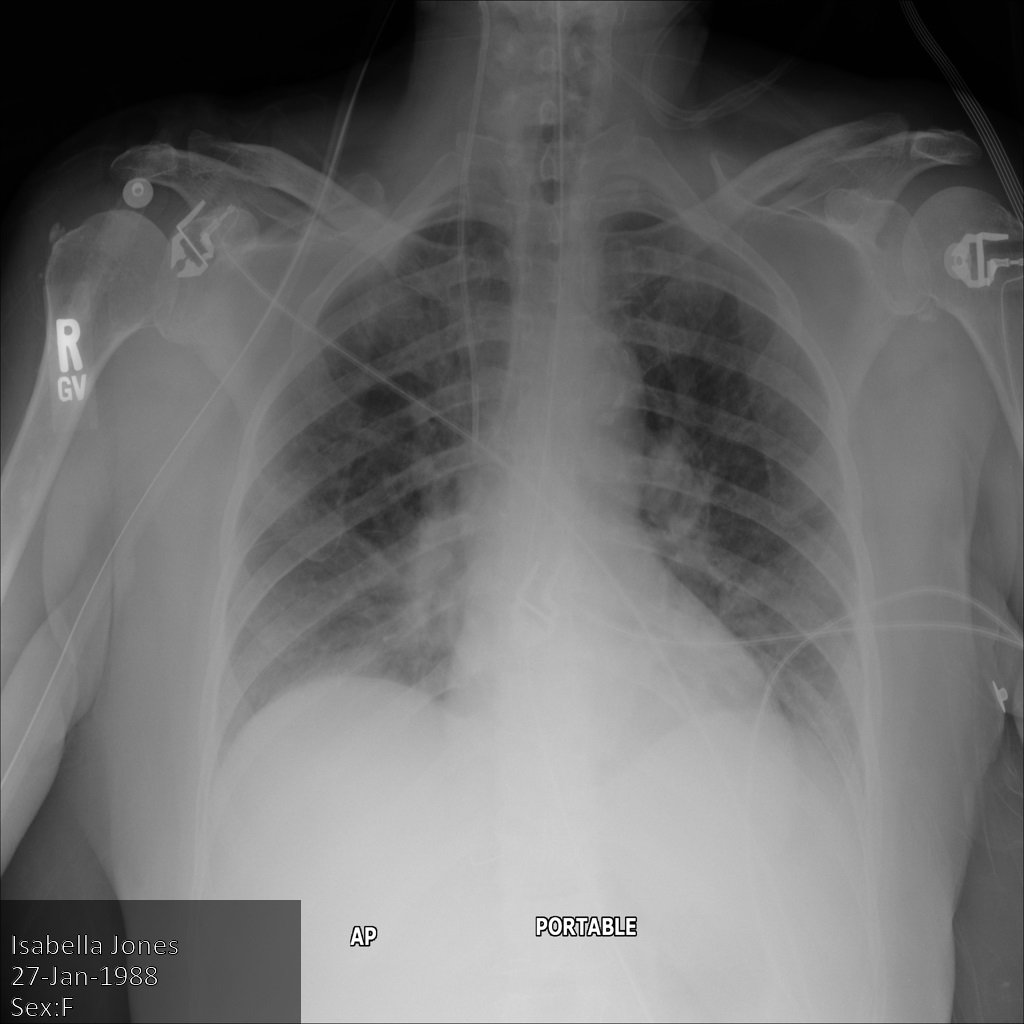

画像にある焼き付き機密テキストのみを秘匿化する

次のサンプルは、データセット内の DICOM 画像にある焼き付き機密テキストを秘匿化する方法を示しています。そのためには、TextRedactionMode フィールドに REDACT_SENSITIVE_TEXT を指定します。

REDACT_SENSITIVE_TEXT を指定すると、デフォルトの DICOM infoTypes で指定された infoType が秘匿化されます。次の秘匿化のために、2 つの追加のカスタム infoType も適用されます。

- カルテ番号(MRN)などの患者 ID

- 登録番号

次の画像は、患者の X 線を秘匿化していない状態を示しています。

REDACT_SENSITIVE_TEXT オプションを使用して Cloud Healthcare API に画像を送信すると、画像は次のように表示されます。

次のことを確認できます。

- 画像の左下にある

PERSON_NAMEが秘匿化された - 画像の左下にある

DATEが秘匿化された

患者の性別は、デフォルトの DICOM infoTypes に従って機密テキストと見なされないため、秘匿化されませんでした。